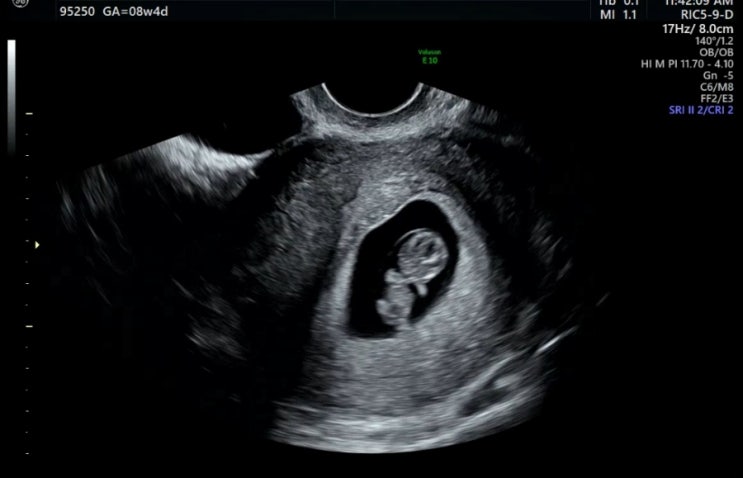

임신 7-8주차 초기 일상 : 입덧없는 임산부 서울여행 김장 하리보 곰젤리아기 초음파

임산부의 60%는 입덧을 한다는데 저는 다행히 입덧 없이 지나가는 중입니다~ 그래서 밥도 잘 먹고, 서울여...